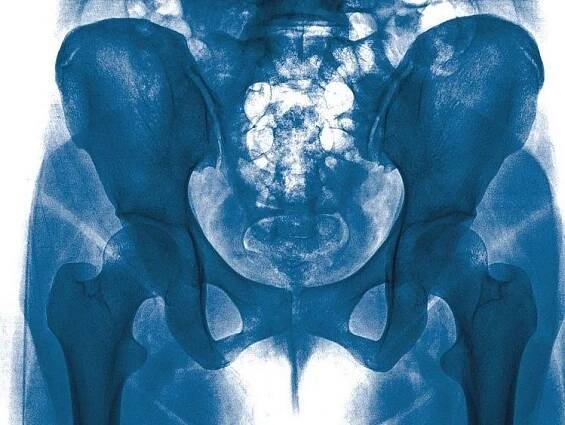

Proč se objevuje bolest kyčle v těhotenství?Během těhotenství výrazně vzrůstají hladiny estrogenu, progesteronu a relaxinu. To způsobuje rozvolnění měkkých tkání. Zvýšená pohyblivost se pak může projevit bolestí. Dalším problémem je rostoucí hmotnost maminky a zvyšující se zátěž, kterou musí kyčle snášet.

Proč v těhotenství měknou klouby a vazivové tkáně?Za to zodpovídá hormon relaxin, který je v těle těhotné ženy produkován ve vysokém množství. Relaxin způsobuje rozvolnění vazivových tkání, čímž se tělo připravuje na porod. Pánev je díky tomu pružnější a dítě pak může během porodu bez problémů projít porodním kanálem.